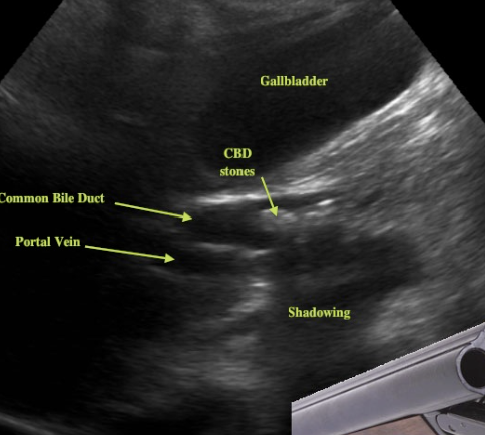

what is shown?

target or donut sign associated with intussusception

pseudokidney sign (intussusception- long axis)

sandwich sign (intussusception- long axis)